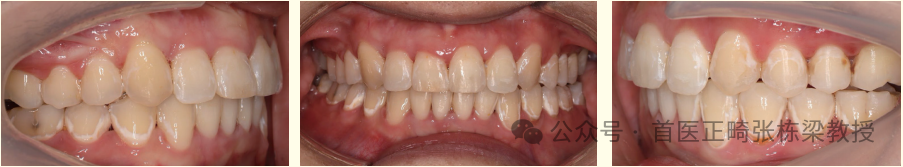

(1)垂直向增加后牙高度,打开前牙咬合,内收直立上下前牙。

增加后牙高度,内收上下前牙,增加面下 1/3 距离,改善面型

对于很多患者不拔牙矫治是可以改变面型的,拔除上下智齿,控制好上前牙转矩,和下颌后部平面角度,是可以改变面型的。但需要足够长的治疗时间,而且有可能远超过拔牙矫治的时间。